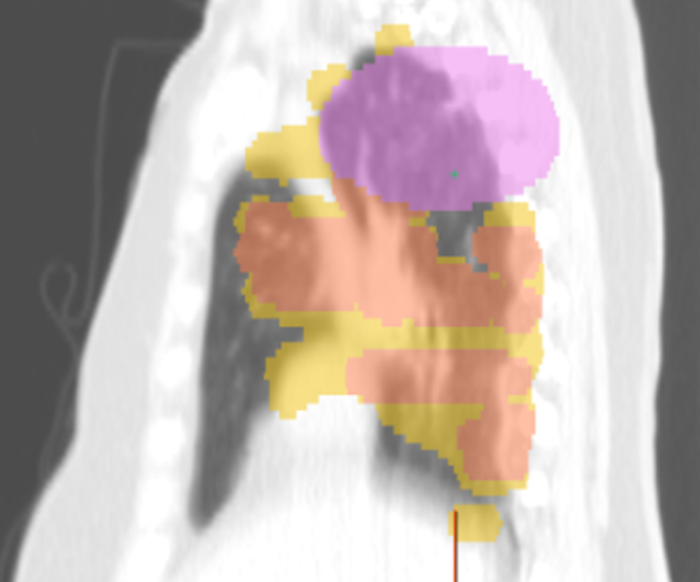

Stereotactic Body Radiation Therapy (SBRT) is a widely used, non-invasive treatment for early-stage non-small cell lung cancer (NSCLC), particularly in medically inoperable patients. While SBRT is generally well tolerated, a subset of patients – estimated at 6–12% – have underlying interstitial lung disease (ILD), a condition that significantly increases the risk of radiation-induced lung toxicity. Prior studies have shown that patients with ILD are at a markedly higher risk of developing radiation pneumonitis, with severe (grade 3) and even fatal (grade 5) toxicities occurring at much higher rates compared to patients without ILD. Despite these known clinical risks, the radiographic manifestations of SBRT-induced lung injury – especially the progression of fibrosis outside the irradiated field – remain poorly understood.

This retrospective study aims to deepen our understanding of SBRT-related toxicity in patients with ILD by analyzing radiographic and clinical data to evaluate whether SBRT triggers accelerated pulmonary fibrosis outside the irradiated area in patients with ILD. The study leverages advanced imaging analysis tools and computational modeling techniques to quantify lung changes and identify predictive imaging biomarkers. These analyses are designed to go beyond traditional clinical assessments and offer a more nuanced, data-driven understanding of radiation-induced lung injury. By integrating radiographic, clinical and computational data, this study seeks to provide a more comprehensive picture of SBRT toxicity in ILD patients. The findings could lead to improved risk stratification, personalized treatment planning and ultimately better outcomes for patients with lung cancer and coexisting ILD.

Dose mask for Stereotactic Body Radiation Therapy (SBRT), a widely used, non-invasive treatment for early-stage non-small cell lung cancer (NSCLC)

Stereotactic Body Radiation Therapy (SBRT), a widely used, non-invasive treatment for early-stage non-small cell lung cancer (NSCLC)